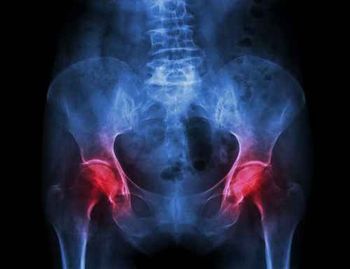

TeleECHO educational programs for healthcare providers have successfully trained physicians and other healthcare providers to fulfill the unmet needs of patients without access to specialty care, particularly osteoporosis care. In this interview with Dr. Michael Lewiecki, he introduces us to Bone Health TeleECHO. He tells us how the program works, why it’s needed and how you can launch one in your state.